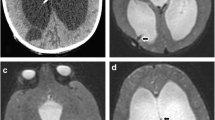

Magnetic resonance imaging (MRI) may offer a further option for investigating suspected shunt malfunction in children. Boyle et al. demonstrated MRI scanning to be of comparable diagnostic accuracy compared with CT scan (81.8% vs 82.4%) in the acute setting of suspected shunt malfunction [7]. MRI image quality has similarly been demonstrated to be excellent or good in 94% of scans performed for assessment of shunt functioning. In a review of 67 MRI scans performed in children with hydrocephalus, Ashley et al. reported identification of shunt catheter tip in over 75% of cases, with good to excellent image quality in around 60% cases [4]. However, the average time of scan was 22 min, over double the average for a CT scan. Young children in particular find long MR acquisition times difficult to tolerate. More recently, faster MRI sequences have been developed to try and overcome this problem [38]. Further limitations to the use of MRI scanning in suspected shunt malfunction would be both the cost, as well as access to an MRI scanner.

Both White et al. and our study demonstrated higher levels of radiation exposure in children under the age of 1 year [37]. Ultrasound examination provides a non-radiating method of assessment of ventricular size in children with suspected shunt malfunction who have a patent fontanelle, and this has been shown to be a reliable method of follow-up in this population by Mandiwanza et al. [17]. Ultrasound has been utilised in other studies to measure optic nerve sheath diameter (ONSD) in paediatric patients with suspected raised ICP [18]. Normal values in the paediatric population have been published, with some studies reporting sensitivities and specificities of 61% and 22% respectively, in detecting shunt malfunction in the paediatric population using ONSD measurements [12]. A recent cross-sectional study performed across 33 units reported notable reductions in the use of CT scanning in paediatric population for a variety of medical presentations, including an increase in the use of USS and MRI in patients with ventricular shunts. Whilst this is a positive step, CT scanning remained the most common imaging modality [23].